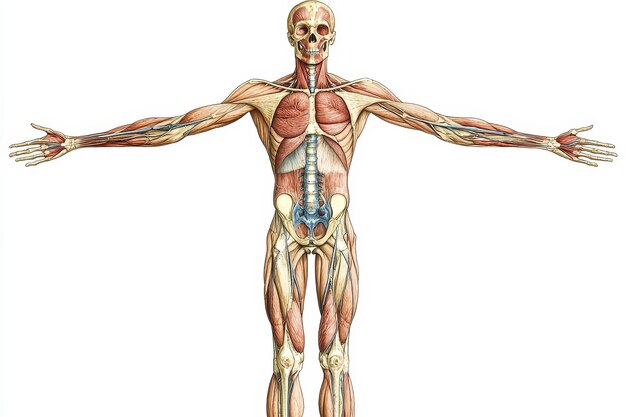

Human Anatomy Illustration With Detailed Muscle An 350529002

14/11/2025

ร่างกายมนุษย์